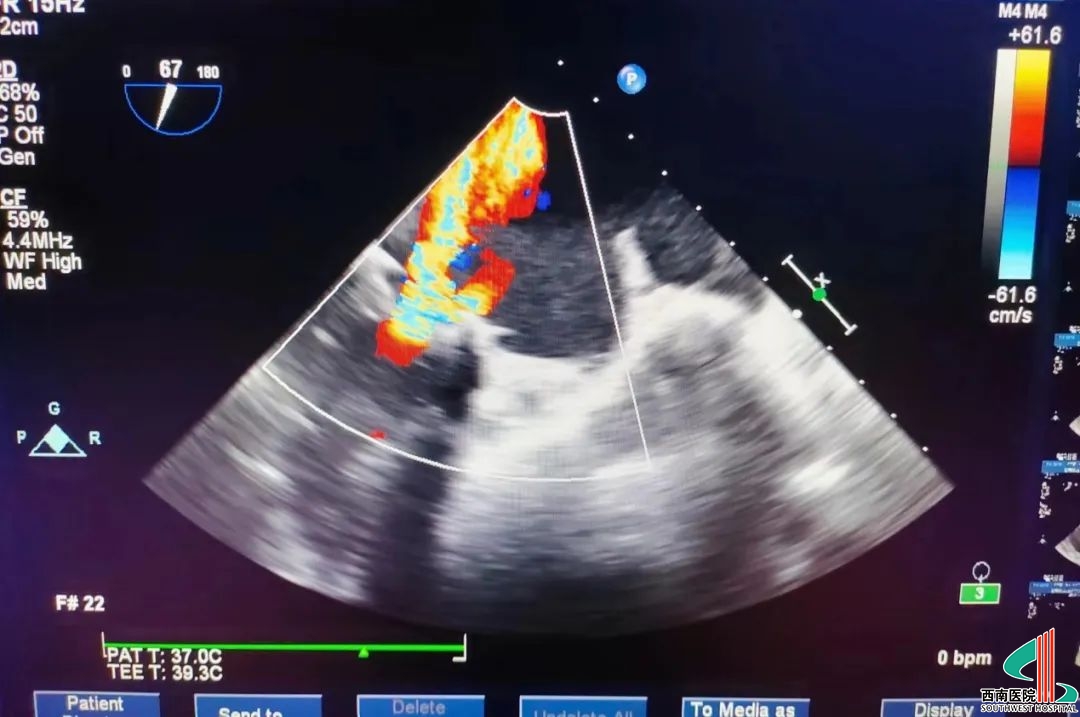

术前食道超声示

术后食道超声示